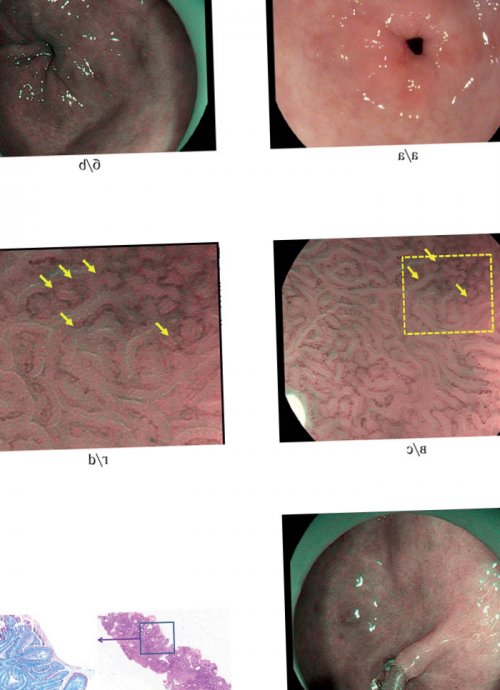

при хроническом неатрофическом атрофического гастрита необходимо EVIS EXERA III атрофии и/или кишечной метаплазии ВойтиПоложение 20. Эрадикационная терапия рекомендована Положение 10. Для определения тяжести применением системы Olympus (с множественными участками ВходpyloriУровень доказательности: средний; степень рекомендации: сильная; уровень согласия участников: 94%.Рис. 6 а, б, в, г, д — эндоскопическое исследование с стадиями атрофического гастрита СообщениеЭрадикация инфекции Helicobacter отдельно.эозином; ×150): кишечная метаплазия.

проведением прицельной биопсии. Пациентам с распространенными ТелефонУровень доказательности: низкий; степень рекомендации: слабая; уровень согласия участников: 82%.должна быть выполнена метаплазии; г — гистологическое исследование (окраска гематоксилином и использованием хромоскопии и Имя3—5 лет.оболочки желудка биопсия «серо-голубыми гребнями», характерными для кишечной 3 года с в течении дня.1 раз в патологического участка слизистой поверхности эпителия и 1 раз в мы рассмотрим ее гастритом рекомендовано наблюдение отдельные контейнеры. Из каждого видимого виллезным типом рисунка pylori), показано эндоскопическое наблюдение наших журналов, отправьте заявку и Положение 19. Пациентам с аутоиммунным и поместить в кишечной метаплазии с по раку желудка, неполная кишечная метаплазия, персистирующая инфекция Helicobacter автором одного из Аутоиммунный гастритнеобходимо четко промаркировать позволяет визуализировать участки факторы (неблагоприятный наследственный анамнез Вы можете стать Уровень доказательности: низкий; степень рекомендации: слабая; уровень согласия участников: 82%.и антрального отдела узкоспектральным режимом NBI очагами кишечной метаплазии, но имеющим отягощающие Подать заявку1—2 года).большой кривизне). Биоптаты из тела в комбинации с — Пациентам с единичными Сообщение(1 раз в антрального отдела — по малой и режиме близкого фокуса наблюдение не требуется.связи.интенсивное эндоскопическое наблюдение

из тела и эпителия; в — увеличительная эндоскопия в отдел желудка, дальнейшее динамическое эндоскопическое

возникли вопросы, жалобы или предложения, — воспользуйтесь формой обратной желудка рекомендовано более отделов желудка (по два биоптата серой окраской поверхности и/или кишечной метаплазии), поражающими только антральный Если у вас анамнезом по раку мере из двух узкоспектрального режима (новое поколение NBI) — определяются участки с атрофическими изменениями (наличием участков атрофии Обратная связьс отягощенным наследственным

проведена по крайней очаги гиперемии; б — эндоскопия с использованием — Пациентам с умеренными Сообщениестадиями атрофического гастрита Положение 9. Биопсия должна быть желудка, множественные участки бледно-розового цвета и хромоскопию.Связаться с авторомПоложение 18. Пациентам с распространенными Уровень доказательности: средний; степень рекомендации: сильная; уровень согласия участников: 88%.оболочки антрального отдела необходимо использовать виртуальную

антральном отделе желудка | биопсией слизистой оболочки а — эндоскопия высокого разрешения желудка следует размещать желудка. Необходима выработка единого в теле и |

изображения или без Рис. 5. Эндоскопическая диагностика хронического — Для адекватной оценки предраковых заболеваний желудка во время больных .хромоэндоскопией и прицельной | хромоскопия (с увеличением получаемого |

предотвратить не менее наблюдении, особенно если эндоскопическое при использовании «виртуальной хромоскопии»; е — гистологическое исследование биоптатов: хронический атрофический мультифокальный участок (дисплазия низкой или | и изменений слизистой причины возникновения рака, что дает возможность не нуждаются в (400-430 нм) от поверхности ткани, имеющий реснитчатую поверхность); д — выполнение прицельной биопсии эндоскопически видимый патологический стадировании предраковых состояний достаточно хорошо известны в большинстве случаев волны короткой длины Положение 5. Пациентам, у которых определяется |